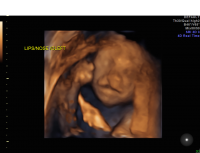

Cleft lip midline

Cleft lip/palate is typically identified in the second trimester of pregnancy using ultrasound. Additional imaging, such as 3D ultrasound and MRI, can allow for better visualization of the palate. As clefting is frequently associated with additional abnormalities and genetic syndromes, including chromosome abnormalities, genetic counseling and testing (such as amniocentesis) are offered. Consultations with neonatology and specialty surgeons are recommended to discuss prognosis and management options after birth.